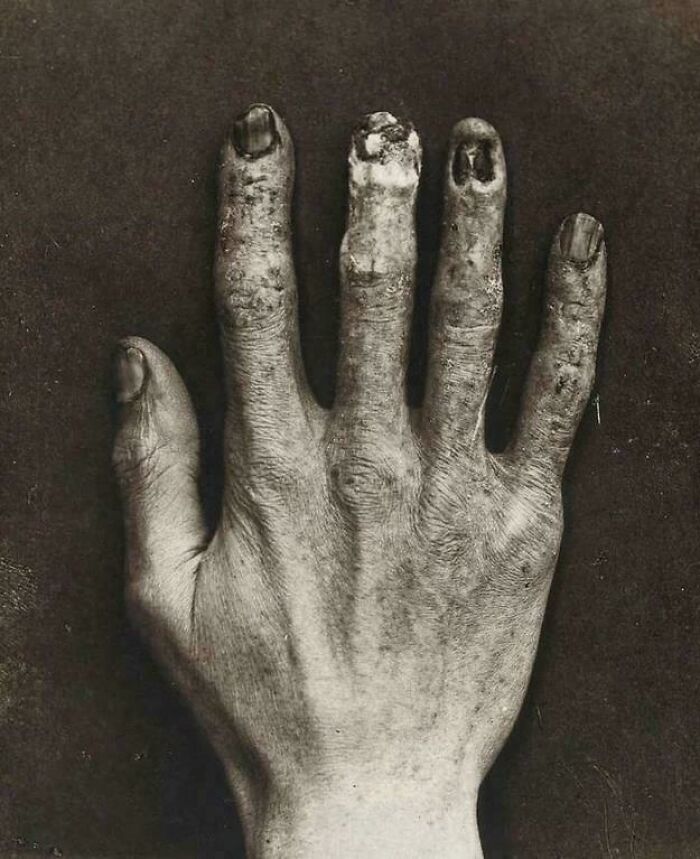

Hand Belonging To An X-Ray Technician At The Royal London Hospital, Which Shows The Damage From Radiation Exposure Back In 1900’s!!

According to Reddit thread: This is the hand of Clarence Dally. An assistant of Thomas Edison’s in his early explorations of x-rays. He is one of the first victims of the harmful effects of x-rays, suffering a prolonged series of radiation related injuries, amputations and eventually succumbing to metastatic cancer. I’m also not sure about the Royal London Hospital claim. I can’t find any supporting information but I have doubts that Dally travelled to England for treatment.